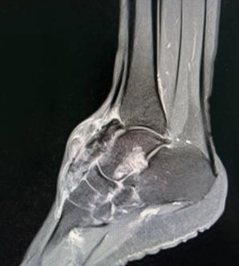

丽姐(化名)患足部腱鞘巨细胞瘤多年,已进行多次手术却又复发,并且肿瘤侵犯关节、累及关节面,严重影响了她的生活质量。

丽姐来到中国医学科学院肿瘤医院深圳医院骨科就诊时,肿瘤范围分布广泛,后确诊弥漫型腱鞘巨细胞瘤。